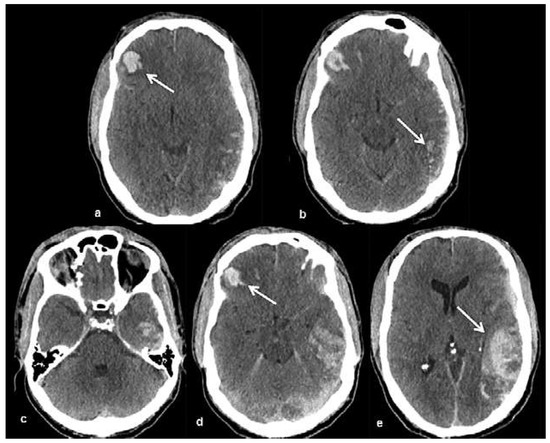

Head and brain trauma: general aspects and neuroimaging

by Johanna Maria Lieb, Christoph Stippich and Meritxell Garcia

Swiss Arch. Neurol. Psychiatry Psychother. 2015, 166(8), 279-292; https://doi.org/10.4414/sanp.2015.00374 - 1 Jan 2015

In this article the general clinical aspects, imaging indications and different injury mechanisms of traumatic brain injury (TBI) are reviewed. In addition, the different imaging modalities and strategies are presented, including more specific imaging features of the various injuries. Computed tomography (CT) is the imaging modality of choice in the acute phase owing to its wide availability and short scanning time, as well as to its high sensitivity for the detection of fractures and acute bleeding. Although magnetic resonance imaging (MRI) is superior to CT in many other aspects, it plays no role in the acute phase. MRI, however, has been proven to be useful and complementary to CT in the subacute and chronic stages as well as in the case of inconclusive results on initial CT. Especially the use of standard sequences like fluid attenuated inversion recovery (FLAIR), diffusion and susceptibility weighted imaging (DWI and SWI) have been shown to increase the diagnostic potency in diffuse axonal injury, in mild brain trauma and also in more chronic stages of TBI. The use of more advanced MRI techniques such as diffusion tensor imaging (DTI), magnetic resonance spectroscopy (MRS), functional MRI (fMRI) and magnetic transfer imaging (MTI) can further complete the diagnostic evaluation and give insights into different pathophysiological processes in TBI. Full article